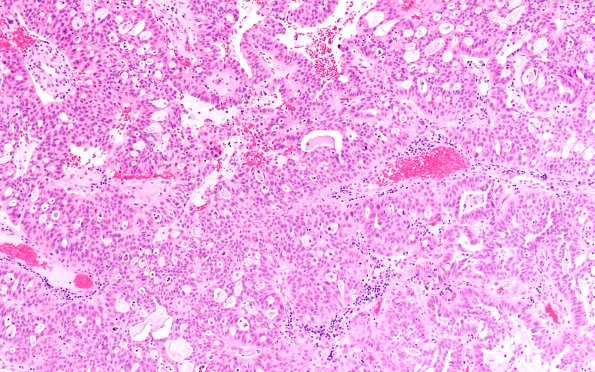

Washington University Experience | NEOPLASMS (METASTASES) | Microscopic | 96A1 Metastasis, Lung adeno (Case 96) H&E 10X

Case 96 History ---- The patient is a 65yo male with a history of lung cancer metastatic to brain. ---- 96A1,2 H&E-stained sections show a moderately differentiated metastatic adenocarcinoma with cribriform and glandular architecture. The cells are moderately pleomorphic with abundant eosinophilic cytoplasm and large oval nuclei with prominent nucleoli. Mitoses are brisk. (H&E)